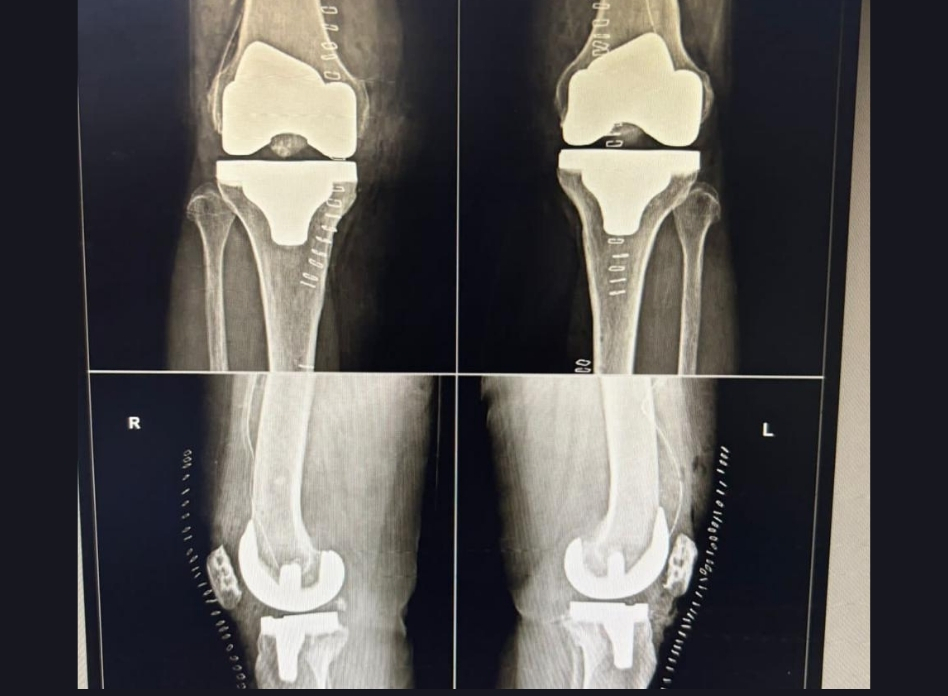

TOTAL KNEE REPLACEMENT SURGERY

Total knee replacement, or TKR, also called knee arthroplasty, refers to a surgical procedure in which a knee joint affected by arthritis is resurfaced with an artificial implant (prosthesis) designed to relieve pain, enhance mobility, and restore the function of the knee. People suffering from severe arthritis or knee joint damage undergo the procedure in an effort to improve their overall knee health.